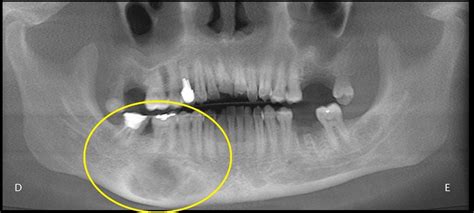

Radiografía mostrando displasia fibrosa

En definitiva, la edad del paciente y el aspecto radiológico de la lesión (densidad esclerosa, insuflación, escasos signos de agresividad y afectación de más de un hueso) apuntan al diagnóstico radiológico de DF.

Los exámenes radiográficos revelaron una imagen circunscrita radiolúcida, unilocular con focos radioopacos, presentándose desde el canino superior hasta la región de tuberosidad maxilar y reabsorción radicular en los dientes.

En la tomografía computarizada (TAC) se observó claramente la alteración de la arquitectura ósea, con una lesión de intensidad mixta, delimitada por un halo hiperdenso involucrando al seno maxilar y desplazando la cortical vestibular, así como un desplazamiento y rompimiento de la pared lateral de fosa nasal y del suelo orbitario ambos del lado derecho.

Basado en las características clínicas, radiográficas y el examen anatomopatológico se estableció el diagnostico de fibroma osificante central.